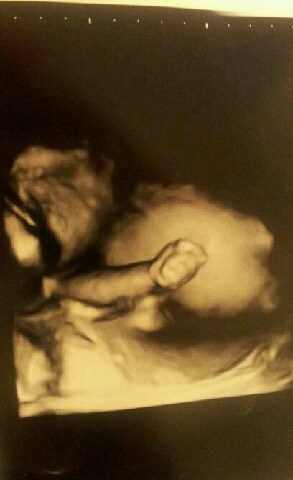

hun ville dog ikke rigtig vise os sit ansigt... men hun havde hånden og fingrene i vejret hele tiden.. fik et super godt billede af hende lille arm og hånd..